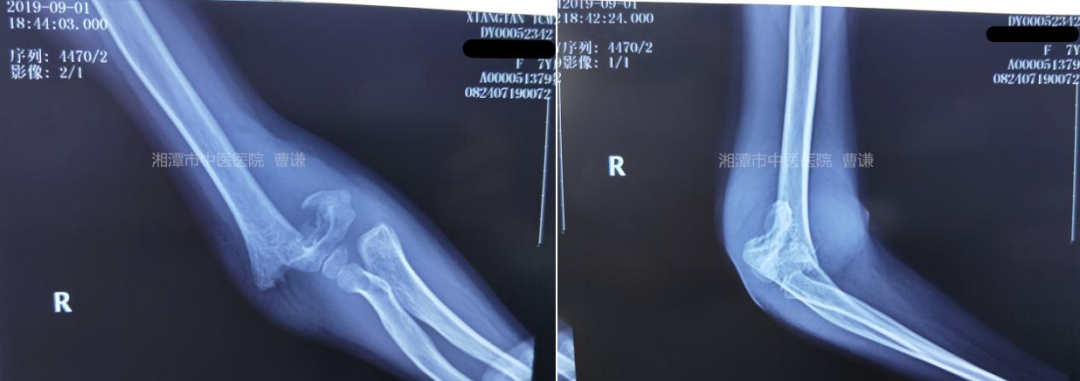

患者性别:女 患者年龄:7 岁 简要病史:跌倒致右肘部畸形、肿痛、活动受限,就诊于我院,拍片诊断为右肱骨髁上骨折。

患者就诊时拍片示右肱骨髁上骨折,断端错位明显。

值班医师予以手法复位小夹板外固定,拍片复查示:断端轻度旋转及桡偏移位。